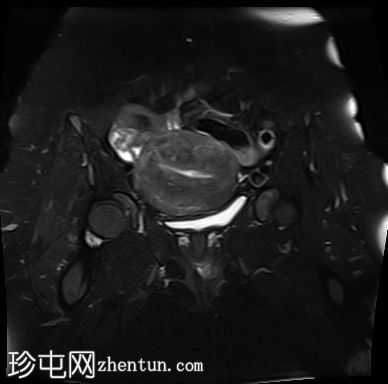

矢状位

T1加权像

子宫肌层前壁可见一小而边界清晰的实性病灶,大小为1.1 × 1.0 cm。该病灶在T1加权像上呈中等信号强度,在T2加权像上呈低信号强度,无强化,无扩散受限。